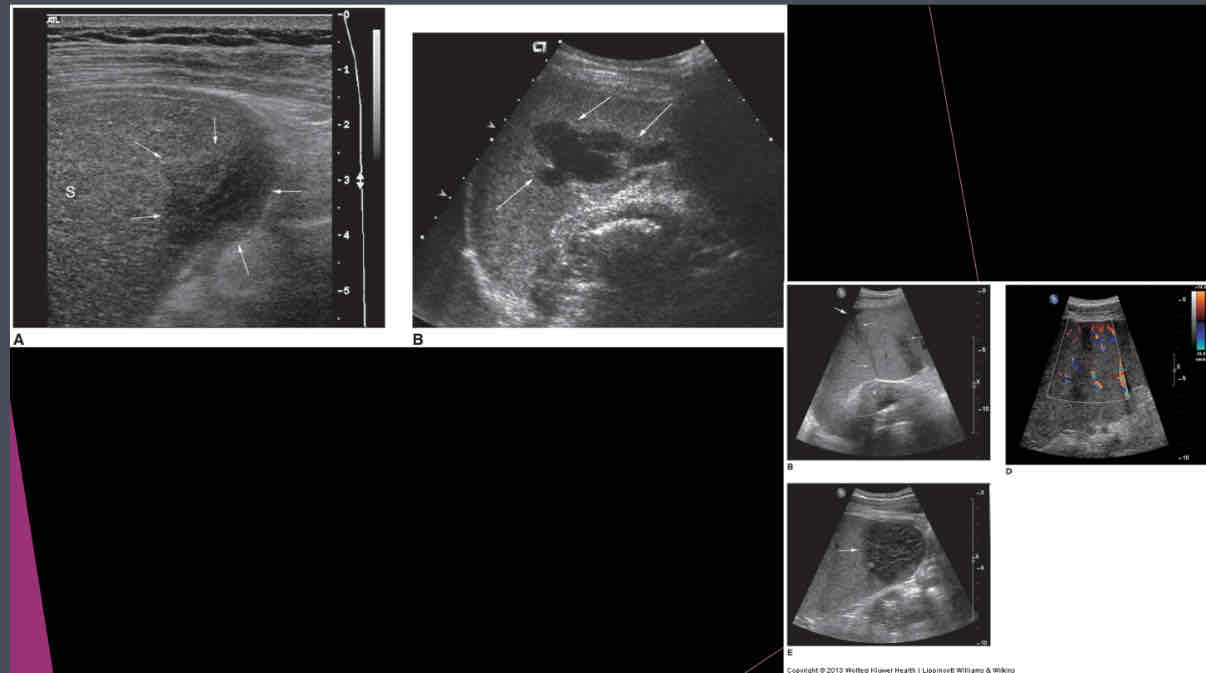

What does the following describe?

•Areas of tissue death, blood supply is cut off

•Found in patients with leukemia, sickle cell anemia, pancreatitis, bacterial endocarditis

•Calcification is last change

splenic infarct

Focused assessment with Sonography for trauma (FAST) – used in ER to determine what?

if free fluid is in the peritoneal cavity

True/False: Fractured spleen may appear only as enlarging spleen with normal echogenicity; blood might be found in pelvis, flanks, Morrison pouch, lesser and greater sacs.

true

What is the condition of the capsule?

-intra-parenchymal or sub-capsular hematoma

-Subcapsular hematoma may appear as normal spleen, or hypoechoic, or echogenic mass adjacent to clearly defined capsule

capsule remains intact

What is the condition of the capsule?

-intraperitoneal or peri-splenic hematoma

-Fluid localized around spleen, but may spread within peritoneal cavity

-Pericapsular hematoma may efface smooth contour of splenic capsule

capsule ruptures

What can hematoma be due to?

•Trauma, coagulation disorder

•Ruptured spleen secondary to trauma or enlargement

US appearance of intraperitoneal blood depends on what?

age, amount, and physical state of the clot